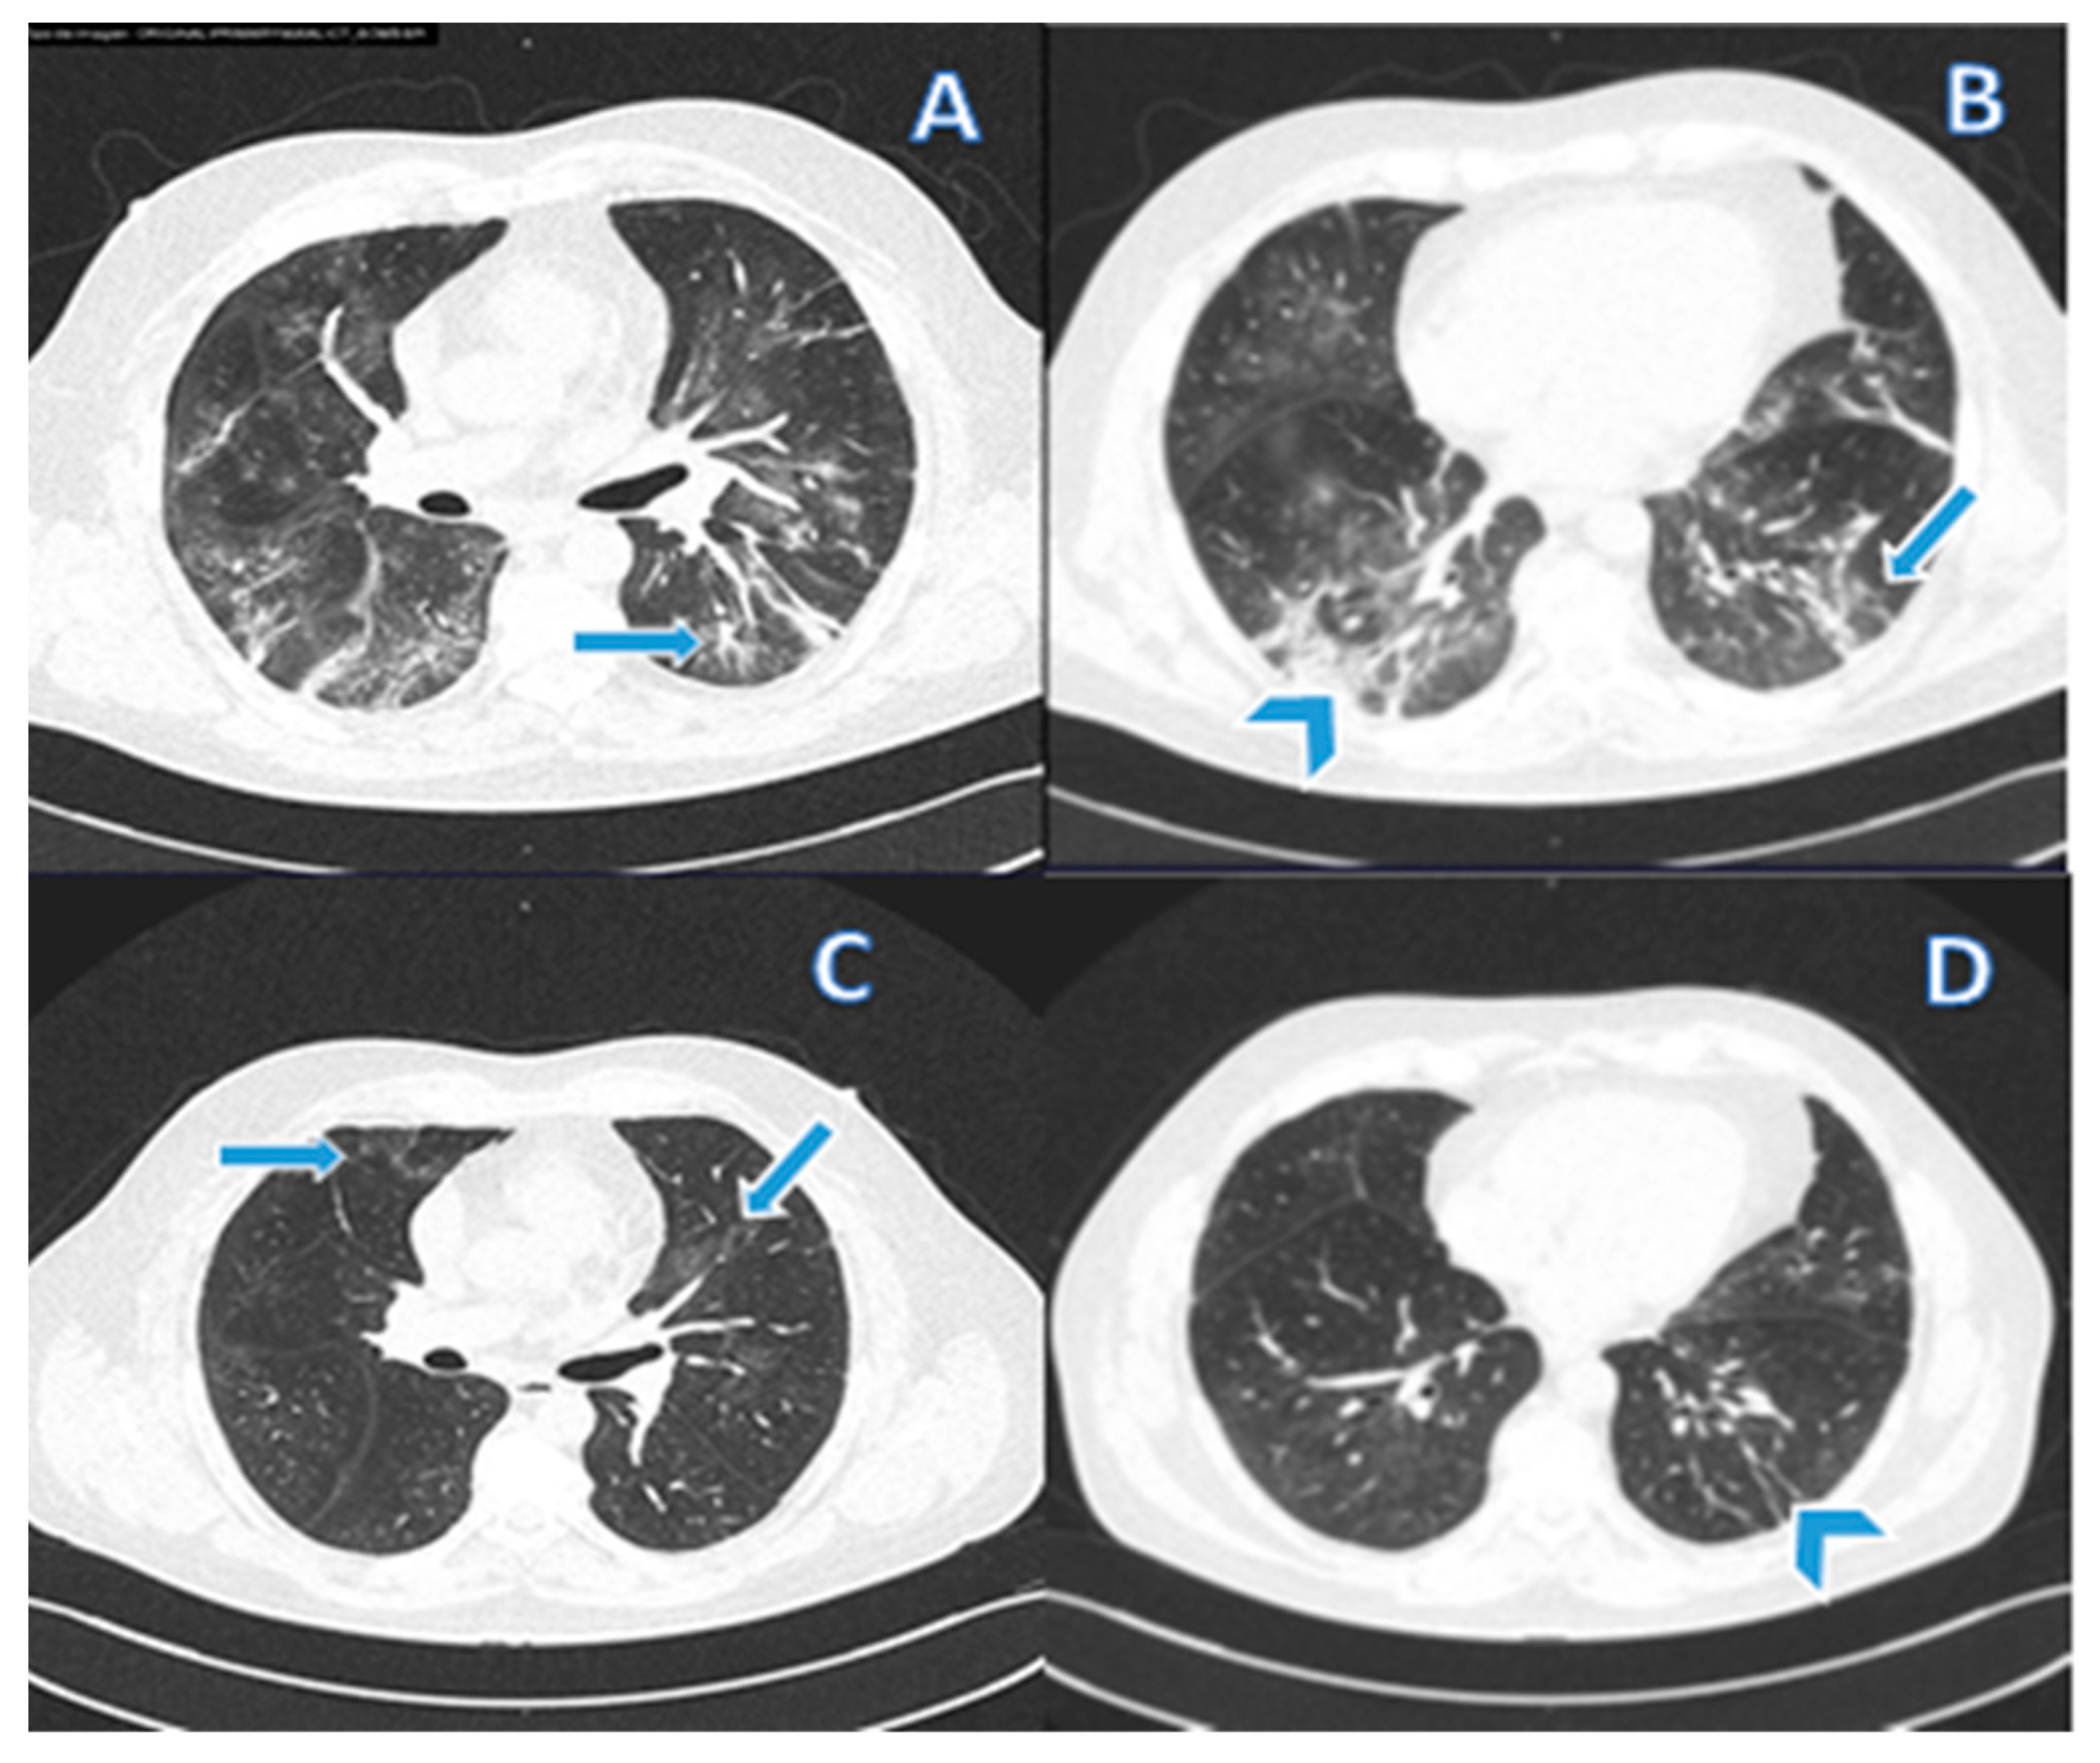

2.3. Post-COVID Assessment of Pulmonary Fibrosis

3.4. Diagnosis of Pulmonary Fibrosis and Risk Factors for the Development of Post-COVID-19 Pulmonary Fibrosis